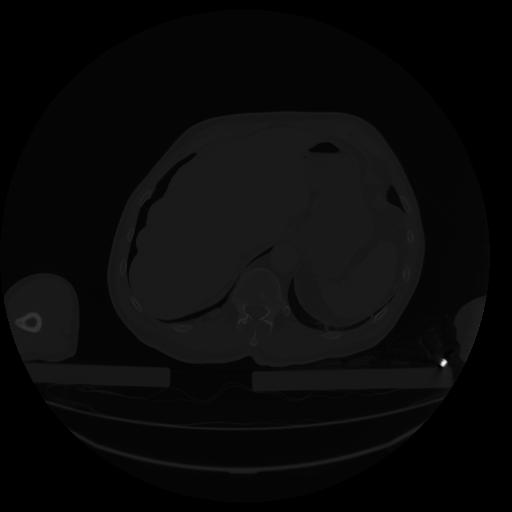

34 CUERPO,CE,Vol,1.0,CUERPO,,